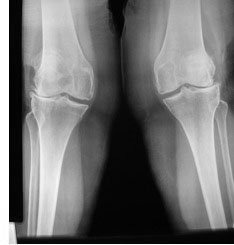

15% are distal femoral osteotomy (also known as var-ising osteotomy) for valgus osteoarthritis where the knee is abnormally knock-kneed like in the lady below. In this case the bone cut is at the lower ('distal') end of the femur (thigh bone).